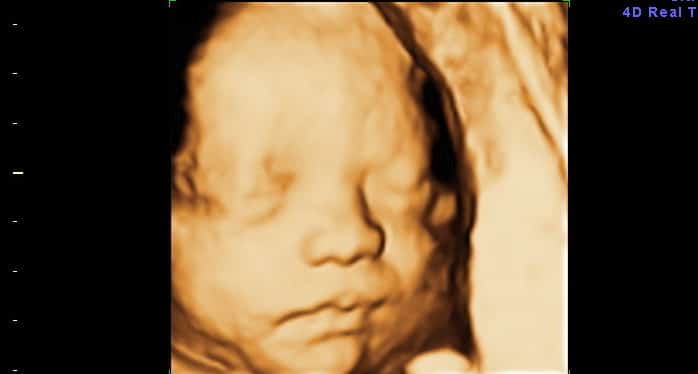

O Bebê Seus órgãos continuam amadurecendo e as unhas e cabelos continuam crescendo. O bebê dorme até 90% do tempo.…